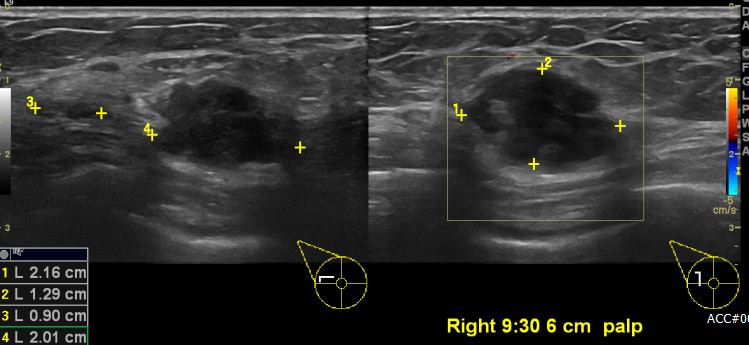

상기환자 우측 유방에 만져지는 멍울있어 내원하시여 우측 9시 30분 방향 6cm

떨어진 거리의 멍울 조직검사 시행하여 우측 침윤성 유관암 진단 되었습니다.